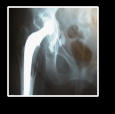

Osteoarthritis, also known as degenerative joint disease (DJD) is a progressive and chronic disease caused by the constant deterioration of a lesion in the articular cartilage of the joint caused by continuous friction which creates bony spurs and cysts on the margins of the joints. As natural wear and tear takes its course, this superficial damage becomes malignant, affecting the entire structure of the joint and destroying its mechanics. Since there is no surgical solution for this stage of the disease, the only solution offered today is joint replacement or Arthroplasty. This is the reason patients suffer years of pain, medication problems, swollen joints, tenderness or redness of joints and limited movement before they are finally operated with a joint prosthesis. Over 70% of people over the age of 65 show some degree of osteoarthritis upon x-ray examinations and according to the World Health Organization (W.H.O), it is predicted that 9.6 %of men and 18% of women over 60 years of age will suffer from Arthrosis, representing the fourth most debilitating disease worldwide. As the population continues to live longer and continue to lead active lives, arthrosis will continue to increase within the population and will demand more pressure from the Medical world to resolve this in a pre-emptive manner, by stemming this chronic, debilitating disease before it affects peoples psychological and physical health. There are countless research papers written about arthrosis discussing the histology, pathology, genetics, environmental factors, body weight, sports related causes, and more, however this research and the investigations haven’t tackled the real issue which is how to treat the initial damage in the articular cartilage of the joints, thus preventing the onset of this degenerative disease. Bio Total Hip is a long overdue innovation that has the potential to not only save on patient costs by a large margin, but more importantly it has the possibility to help people live a pain free lives.